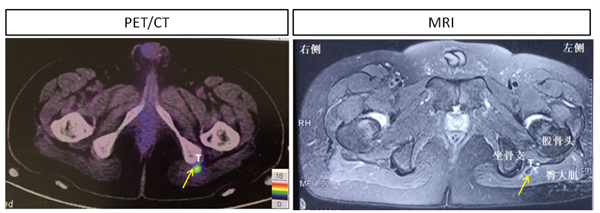

患者是一名30岁成年男性, 1年前无明显诱因双踝疼痛,行走时加重,渐发展至全身多处关节,双髋关节疼痛尤为剧烈,伴有肌肉无力,无法站立行走,夜间卧床翻身困难。曾辗转于省内多家知名三甲医院却无法确诊,进行常规对症处理,镇痛、消肿治疗,并无改善。困惑之中,患者慕名来我院就诊,内分泌科荆爱玉主任医师通过仔细问诊,体格检查,辅助实验室检查,考虑患者为“低磷性骨软化”,给予维生素D3及中性磷酸盐对症治疗,但2个月的疗程并未使患者骨痛、肌肉无力症状好转。通过进一步检查,发现患者左侧臀大肌近坐骨结节处有一个不到2公分的结节状软组织病变,且68Ga-DOTA-NOC摄取异常增高,提示为神经内分泌肿瘤(图2)。在众多的低磷性骨软化的原因中,肿瘤诱导因素非常罕见,唯一有效的治疗方法是手术切除。

图2 利用68Ga-DOTA-NOC PET-CT显像定位诱导低磷性骨软化的软组织肿瘤